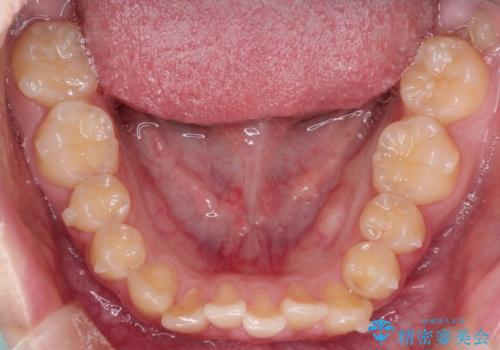

上下の前歯のガタガタを目立たず治したい インビザラインによる見えない矯正

受験生ということもあり、来院頻度が少ないマウスピース矯正で治療が終了できたことに満足いただけました。

上下の正中が一致していませんが、受験を控えているためご本人の希望もあり、いったん終了とさせていただきました。

治療の中断・再開が容易なのもインビザライン治療のメリットといえます。